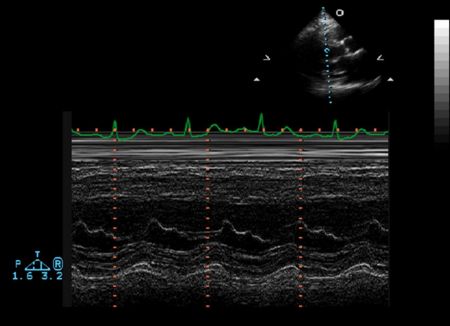

Ventricular M-mode

- Ventricular Wall Thickness

- Ventricular Chamber Size

- Intraventricular Masses